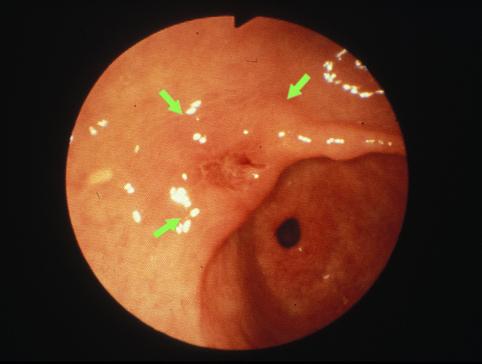

疾患(病理主体)の分類悪性上皮性腫瘍/腺癌

部位(臓器別)胃(部位)/前庭

検査方法内視鏡

腫瘍の肉眼分類0型(表在型)/IIa型(IIa+IIc)

病変の最大径(ミリ)20〜24

腫瘍の深達度sm